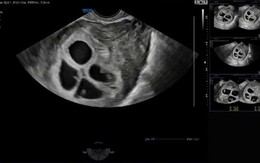

Cực hiếm gặp: Bệnh viện Phụ Sản Hà Nội ghi nhận 1 sản phụ mang thai 4 tự nhiên, tỷ lệ chỉ khoảng 1/700.000 - 800.000 ca

Trường hợp đặc biệt với tỷ lệ hiếm chỉ 1/700.000 ca mang thai tự nhiên khiến giới chuyên môn lẫn cộng đồng không khỏi bất ngờ.